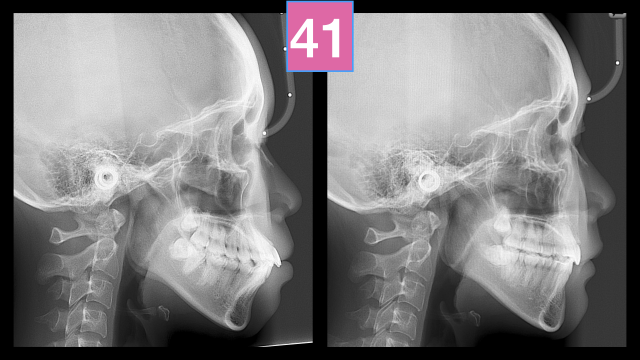

术前检查